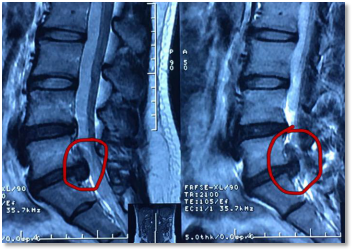

椎间孔镜技术是一种经皮穿刺的脊柱内镜技术,工作套管经自然通道椎间孔或椎板间隙入路,放在硬膜外腔突出物的靶点,在内窥镜直视下摘除突出的髓核组织,双频射频消融残余组织、止血、和利用局部热收缩的原理,封闭破损的纤维环。手术时,病人采用局部麻醉,在完全清醒的状态下,医生和病人之间可以互相交流。手术在可视下进行,术中出血几个毫升,手术后6小时病人即可下床活动。与其它的脊柱微创髓核摘除技术相比,椎间孔镜技术适应症更广、更微创、损伤更小、效果与传统手术相当、恢复更快。

2012年91porn 疼痛科较早在湖北地区引进了椎间孔镜技术,目前已完成手术800余例,取得了良好的治疗效果。随着技术的不断改进及动力系统的应用,脊柱内镜手术除用于腰椎间盘突出症的突出髓核摘除外,也用于治疗颈椎间盘突出症、胸椎间盘突出症及椎管狭窄症。特别对巨大椎间盘突出、脱出、脱垂的病人,实施椎间孔镜下可视、精准、靶向的微创治疗,效果立竿见影,同时保护脊柱的稳定性的。该项技术采用局部麻醉,对老年患者减少了全身麻醉带来的风险,对多节段病变的患者可以微创手术解决问题。